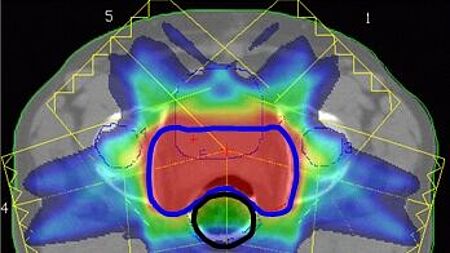

• IMRT and IMAT patient plan verification with OCTAVIUS 4D and VeriSoft